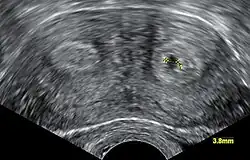

- Clase V: Útero Particionado (Septum uterino o partición).

- Los dos conductos Mullerianos están fusionados pero la separación entre ellos todavía está presente, separando el sistema en dos partes. Con un septum completo la vagina, el cérvix y el útero se pueden separar. Usualmente el septum afecta solo la parte craneal del útero. Un septum uterino es la malformación uterina más común y la causa de muchos abortos espontáneos. Es diagnosticado por técnicas de imágenes médicas como ecografía o resonancias magnéticas (MRI por sus siglas en inglés). La resonancia magnética (MRI) es considerada la mejor herramienta de diagnóstico debido a sus capacidades de multiplanos así como también su habilidad de evaluar el contorno uterino, zona nodal, y otras anatomías pélvicas. Un histerosalpingograma no es considerado de utilidad debido a su inhabilidad para evaluar el contorno exterior del útero y distinguir entre un bicornio y un útero particionado.

Aparte del examen físico, el doctor necesitará tomar imágenes para determinar las características de la malformación: Ultrasonografía ginecológica, resonancia magnética (MRI) pélvica o histerosalpingografía. Un histerosalpingograma no es considerado de utilidad debido a su inhabilidad para evaluar el contorno exterior del útero y distinguir entre un bicornio y un útero particionado. Adicionalmente una laparoscopia y/o histeroscopia pueden ser recetados. En algunos pacientes el desarrollo vaginal puede ser afectado. Al contrario de lo que pudiera pensarse, esta "malformación" no representa incomodidad alguna para la persona que la presente.